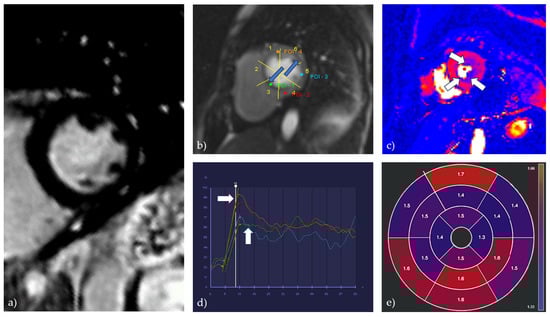

4.1.5. Cardiac Magnetic Resonance (CMR)

- Zdravkovic, M.; Klasnja, S.; Popovic, M.; Djuran, P.; Mrda, D.; Ivankovic, T.; Manojlovic, A.; Koracevic, G.; Lovic, D.; Popadic, V. Cardiac Magnetic Resonance in Hypertensive Heart Disease: Time for a New Chapter. Diagnostics 2022, 13, 137. [Google Scholar] [CrossRef]

- Engblom, H.; Xue, H.; Akil, S.; Carlsson, M.; Hindorf, C.; Oddstig, J.; Hedeer, F.; Hansen, M.S.; Aletras, A.H.; Kellman, P.; et al. Fully quantitative cardiovascular magnetic resonance myocardial perfusion ready for clinical use: A comparison between cardiovascular magnetic resonance imaging and positron emission tomography. J. Cardiovasc. Magn. Reson. 2017, 19, 78. [Google Scholar] [CrossRef] [PubMed]

- Zorach, B.; Shaw, P.W.; Bourque, J.; Kuruvilla, S.; Balfour, P.C.; Yang, Y.; Mathew, R.; Pan, J.; Gonzalez, J.A.; Taylor, A.M.; et al. Quantitative cardiovascular magnetic resonance perfusion imaging identifies reduced flow reserve in microvascular coronary artery disease. J. Cardiovasc. Magn. Reson. 2018, 20, 14. [Google Scholar] [CrossRef]

- Thomson, L.E.; Wei, J.; Agarwal, M.; Haft-Baradaran, A.; Shufelt, C.L.; Mehta, P.K.; Gill, E.B.; Johnson, B.D.; Kenkre, T.; Handberg, E.M.; et al. Cardiac magnetic resonance myocardial perfusion reserve index is reduced in women with coronary microvascular dysfunction. A National Heart, Lung, and Blood Institute-sponsored study from the Women’s Ischemia Syndrome Evaluation. Circ. Cardiovasc. Imaging 2015, 8, e002481. [Google Scholar] [CrossRef]

- Rahman, H.; Scannell, C.M.; Demir, O.M.; Ryan, M.; McConkey, H.; Ellis, H.; Masci, P.G.; Perera, D.; Chiribiri, A. High-Resolution Cardiac Magnetic Resonance Imaging Techniques for the Identification of Coronary Microvascular Dysfunction. JACC Cardiovasc. Imaging 2021, 14, 978–986. [Google Scholar] [CrossRef] [PubMed]

- Chang, A.; Kang, N.; Chung, J.; Gupta, A.R.; Parwani, P. Evaluation of Ischemia with No Obstructive Coronary Arteries (INOCA) and Contemporary Applications of Cardiac Magnetic Resonance (CMR). Medicina 2023, 59, 1570. [Google Scholar] [CrossRef] [PubMed]